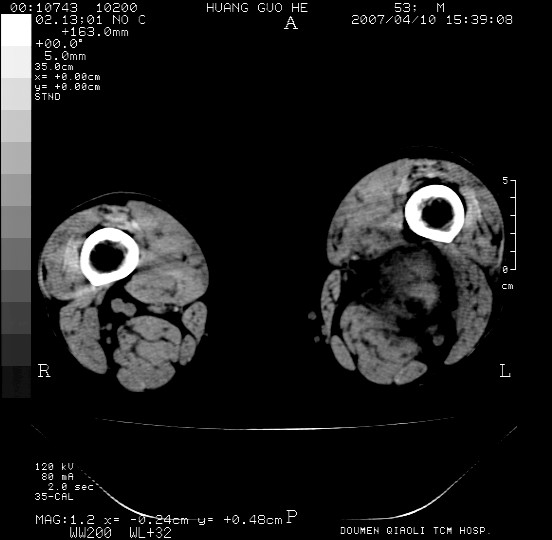

男性,左腘窝包块五个月,逐渐增大,疼痛功能受限,无发热。

查:远端血供差,质地硬。

左侧膝关节后国窝处略低密度软组织肿块,边界清楚,内见脂肪密度及高密度影.多考虑:软组织肿瘤_首选:脂肪纤维瘤.

左侧腘窝软组织肿块,边缘清晰,其内密度不均,周围骨组织无破坏,病灶增长较快,考虑:恶性病变(腘窝滑膜肉瘤可能),建议穿刺活检。